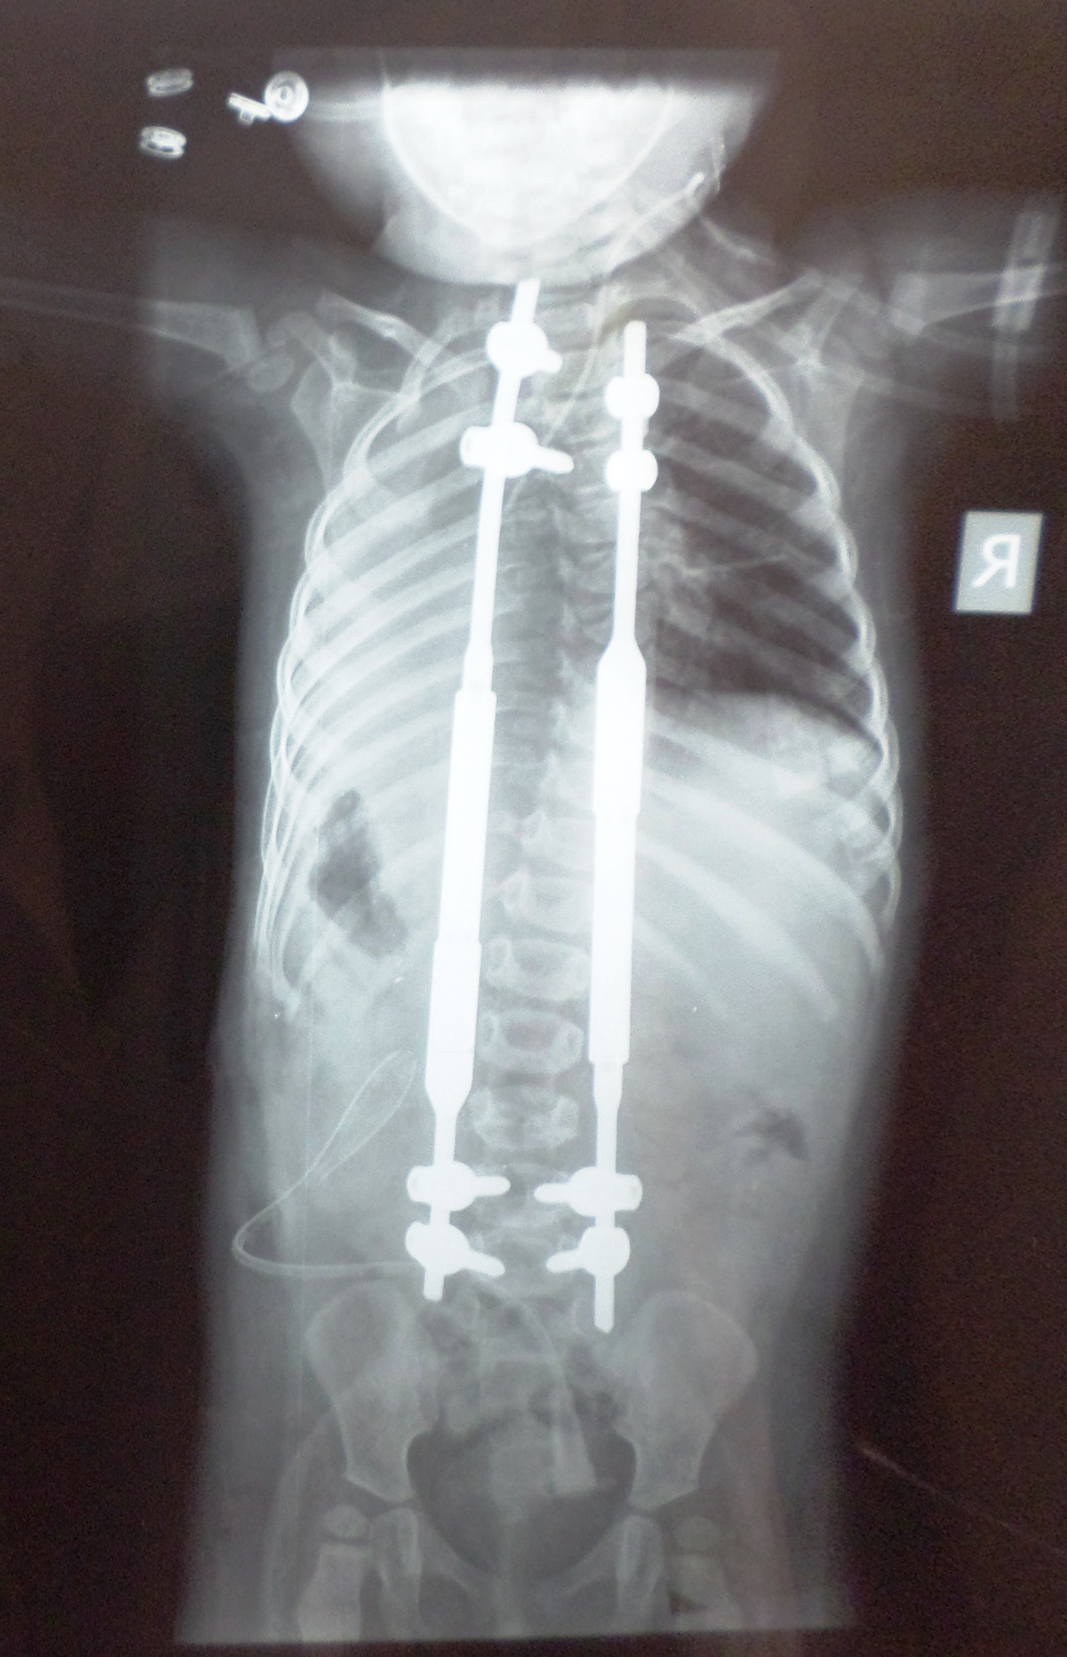

Farklı tipte skolyozu olan hastaların ameliyat öncesi ve sonrası fotoları: